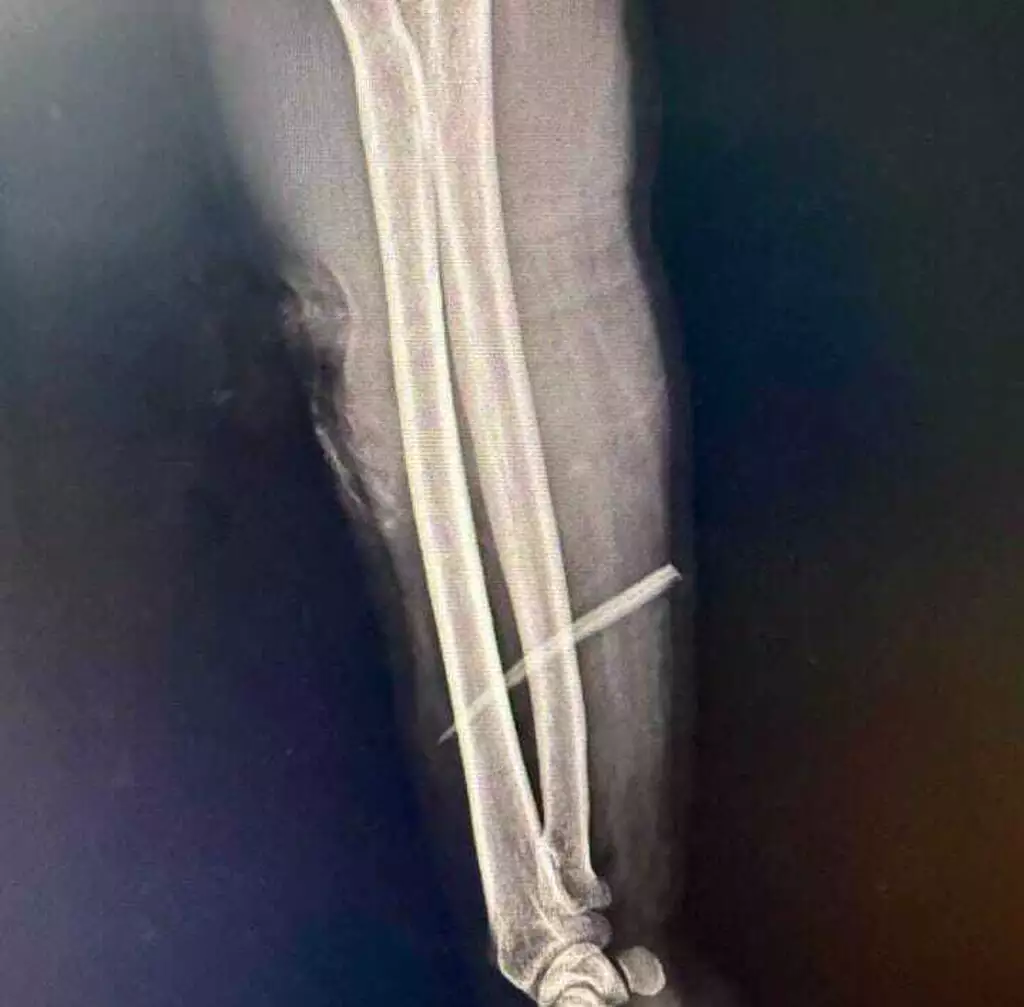

Erasmo Luiz Portilho, de 46 anos, foi pescar no rio Aquidauana, em Camisão, na noite de quarta-feira (10) e acabou atingido pelo ferrão de um peixe. O pescador está internado há três dias com o ferrão cravado no braço e corre risco de perder o membro. A cirurgia para a retirada está marcada para as 15h desta sexta-feira (12).

Segundo o filho, Kauan Nantes Portilho, 18 anos, cantor e compositor, o pai perdeu muito sangue ainda no local do acidente e só sobreviveu porque recebeu atendimento rápido. “Já estava bastante escuro onde está o ferrão. Os médicos disseram que quanto mais demora, maior é o risco de perder o braço”, contou.

Antes de chegar à Santa Casa da Capital, na manhã desta sexta-feira, Erasmo foi atendido no Hospital Regional de Aquidauana e transferido em vaga zero para Campo Grande. “Faz três dias com o ferrão do pintado lá no braço. Agora diz que vai operar às 15h. Estamos na expectativa. Mesmo com a operação, vamos precisar esperar abrir a região para ver se não afetou nenhum nervo e aí ver se vai conseguir voltar ao normal. Como ele perdeu muito sangue no local onde aconteceu o acidente, se demorasse, ele nem chegava. Praticamente nasceu de novo”, relatou o jovem.

Braço do pescador após ser atingido por ferrão (Foto: Arquivo Pessoal)